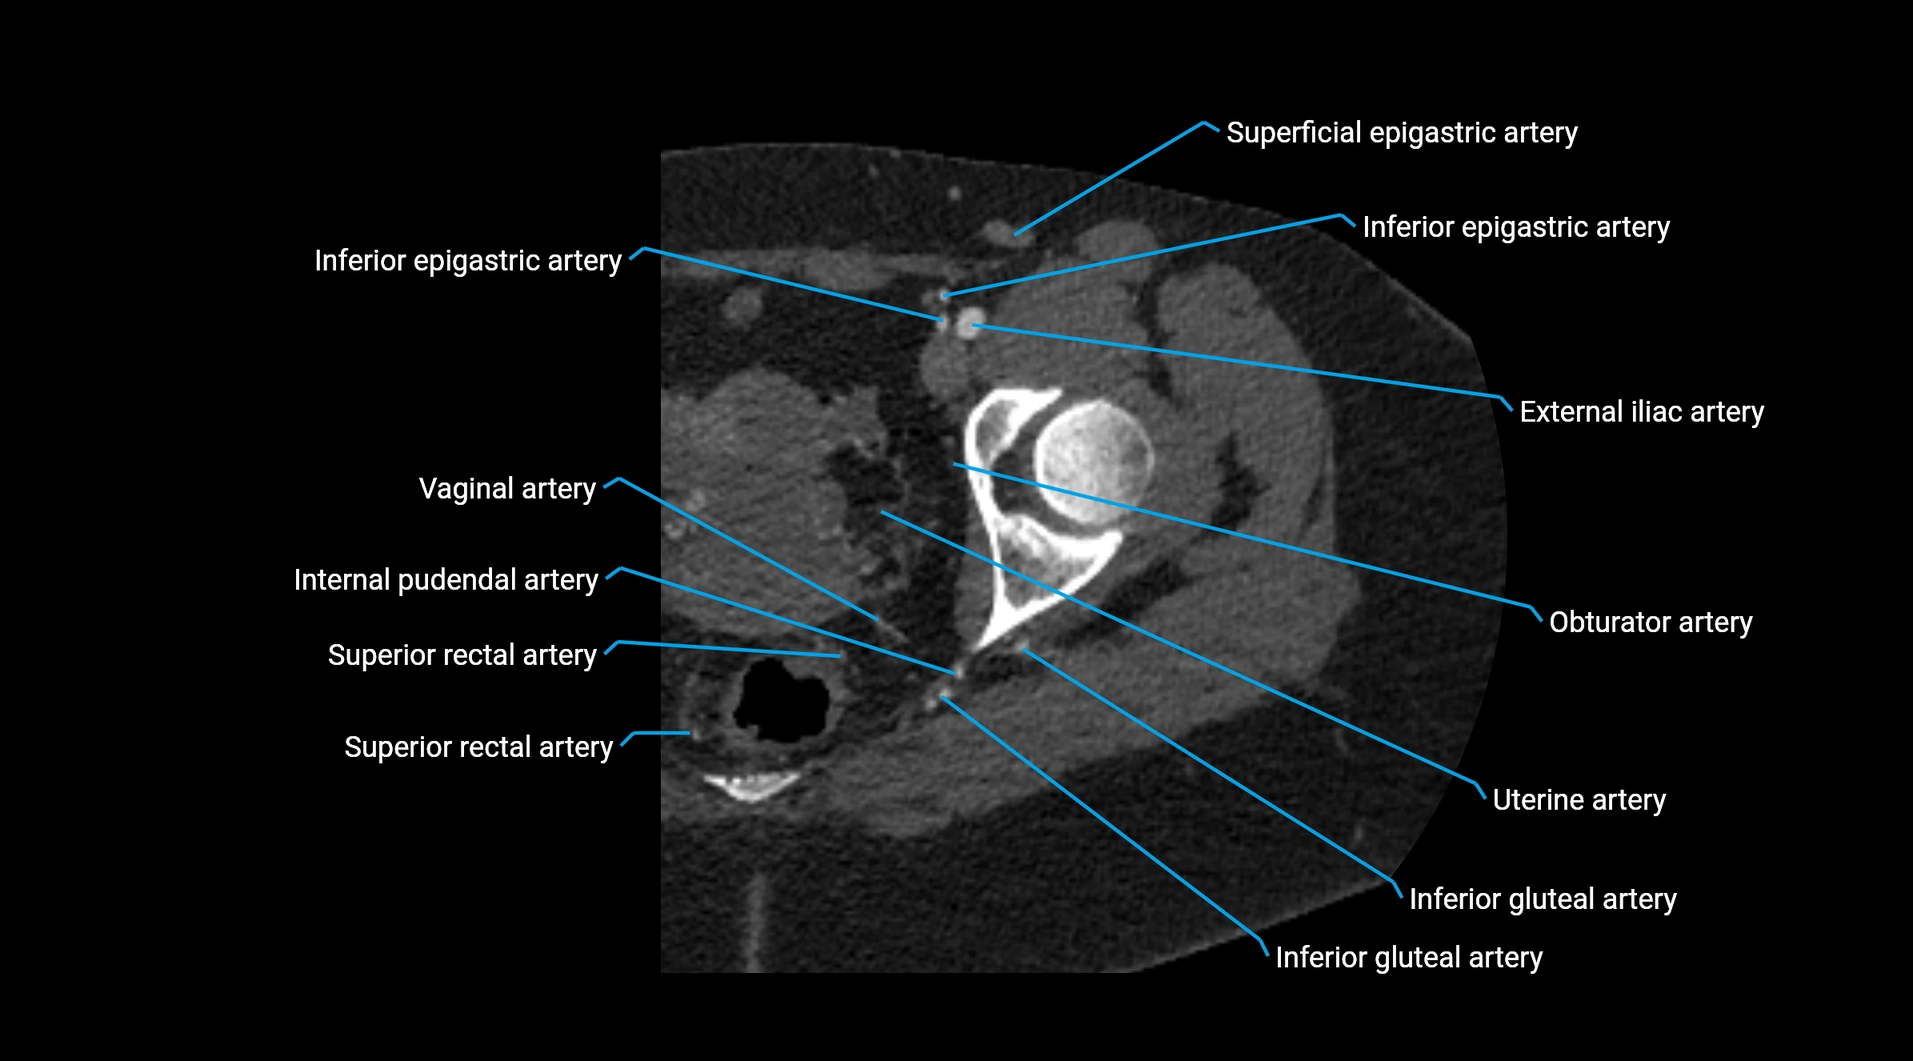

CT images

image